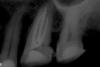

Len@ Опубликовано 24 октября, 2010 Поделиться Опубликовано 24 октября, 2010 Здравствуйте. Нужен ваш совет. Три подряд зуба с одинаковой анатомией и не могу найти МВ2. Подскажите где искать. на последнем снимке прослеживается доп канал. Ссылка на комментарий

zybnaya feya Опубликовано 24 октября, 2010 Поделиться Опубликовано 24 октября, 2010 (изменено) Здравствуйте. Нужен ваш совет. Три подряд зуба с одинаковой анатомией и не могу найти МВ2. Подскажите где искать. на последнем снимке прослеживается доп канал.Искать- то можноно МБ1 очень широкие во всех трех случаях(сужу исключительно по конусности,может и необьективно) возможно получится так,что вы и найдете устья,но в верхней трети МБ2 соединится с МБ1. ПыСы-эндо классное! Я на последнем снимке не вижу никаких дополнительных каналов Изменено 24 октября, 2010 пользователем zybnaya feya Ссылка на комментарий

Kivilgar Опубликовано 24 октября, 2010 Поделиться Опубликовано 24 октября, 2010 ПыСы-эндо классное! Я на последнем снимке не вижу никаких дополнительных каналов +1. Да и нет там возможно МБ2 или засклерозировалось напрочь. Упорно ища как бы дно не перфонуть Ссылка на комментарий

Len@ Опубликовано 24 октября, 2010 Автор Поделиться Опубликовано 24 октября, 2010 Искать- то можноно МБ1 очень широкие во всех трех случаях(сужу исключительно по конусности,может и необьективно) возможно получится так,что вы и найдете устья,но в верхней трети МБ2 соединится с МБ1. Устья действительно широкие, но в зеркале не видать никакого намека на 2 -е устье. ПыСы-эндо классное! Я на последнем снимке не вижу никаких дополнительных каналов. Спасибо. На визиографе лучше видно и мне видится отдельный корень. Ссылка на комментарий

Снежана Опубликовано 24 октября, 2010 Поделиться Опубликовано 24 октября, 2010 http://i007.radikal.ru/1010/af/50d019699837.jpgвот здесь с большей долей вероятности есть мб2, остальные снимки ни о чем... на втором - стандартная укладка, вообще не разложен медиальный корень, про третий - можно с уверенностью сказать, что у пациента зубы есть) не более. На всех снимках не вошла в кадр периапикальная зона небного корня, поверните датчик вертикально. Ссылка на комментарий

x3m Опубликовано 24 октября, 2010 Поделиться Опубликовано 24 октября, 2010 вот здесь с большей долей вероятности есть мб2, +1сфоткать бы еще: тубус горизонтальнее и от пятерки - см. уровень раздвоения периодонтальной щели мез.корня Ссылка на комментарий